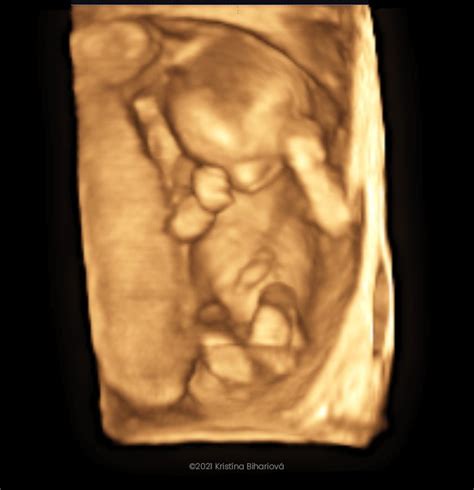

3D/4D Ultrazvuk

Ide o špeciálne zobrazenie bábätka, ktoré vidíte trojrozmerne. Z takéhoto vyšetrenia vám zvyčajne lekár natočí video, na ktorom vidíte aj pohyb dieťatka v reálnom čase. Môžete vidieť, aké má vaše bábätko črty, či dokonca na koho sa podobá. Samozrejme, toto vyšetrenie má svoje limity, nie vždy je úplne zreteľné a vydarené, ale medzi budúcimi mamami je pomerne obľúbené. Lekár vám môže aj vytlačiť 3D fotografiu dieťatka.